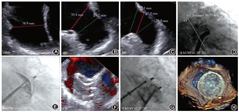

3例在完成LAA造影后,放弃尝试植入PLO,择期行LAmbre封堵器补救,2例成功(1例使用最大型号LAmbre封堵器36 mm×40 mm ,1例使用特殊型号LAmbre封堵器18 mm×32 mm,图10),1例使用2个LAmbre封堵器但仍封堵失败(图11)。

6例尝试植入PLO不成功,行补救性DLO植入,均成功封堵,使用LAmbre封堵器5例和Leftear封堵器1例。其中3例使用较大型号封堵器(图12),31 mm×35 mm 1枚(Leftear封堵器)和36 mm×40 mm 2枚,1例使用最小型号LAmbre封堵器(图13)16 mm×22 mm、2例使用特殊型号LAmbre封堵器24 mm×36 mm及22 mm×34 mm。

值得注意的是,发生冠状动脉压迫3例(0.5% ),均为PLO组(3/328, 0.9% ),且均为植入Lefort封堵器(3/81, 3.7% ),观察到患者出现胸闷症状及心电图改变。1例封堵器未释放,予全回收,观察到出现心包积液,中等量,未出现填塞,迅速再次植入Lefort封堵器,后观察症状稳定,未予心包穿刺,围手术期无其他并发症。2例在Lefort封堵器释放后发现压迫冠状动脉,造影提示1例压迫到左主干末端分叉处,行补救性PCI治疗[17];1例压迫到LCx近端,仅LCx行补救性PCI治疗(图14)。

封堵器脱落1例(0.2% )。患者植入22 mm×28 mm LAmbre封堵器,满足COST原则后释放封堵器,密封盘稍移位致出现>5 mm的残余分流,考虑封堵器可能存在脱落风险。使用Fustar可调弯鞘管(先健科技公司,深圳)及普通一次性活检钳回收封堵器时出现封堵器掉落,并进入降主动脉系统,顺利回收。并再次植入新的22 mm × 28 mm LAmbre封堵器1枚(图15)。